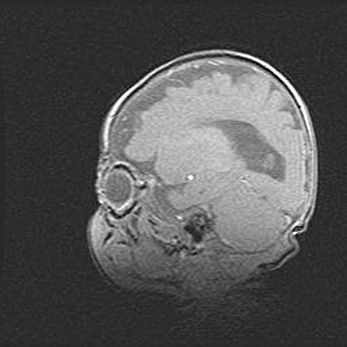

Сообщающаяся гидроцефалия. Кистозная энцефаломаляция головного мозга.

Возраст: 3 месяца 4 дня

Вес: 3100 г

Пол: женский

Окружность головы: 34 см

Срок гестации: 31 неделя

Кистозная энцефаломаляция головного мозга - одна из форм поражения головного мозга в детском возрасте. Характеризуется возникновением множественных и распространённых кист в коре, белом веществе и подкорковых образованиях головного мозга у плодов, новорождённых и детей раннего возраста. Развитие кистозной энцефаломаляции связано с внутриутробной асфиксией и гипотонией, родовой травмой, тромбозом синусов, пороками развития сосудов, инфекциями, сепсисом и другими причинами. Наиболее значимые инфекционные агенты: вирусы простого герпеса, цитомегалии, краснухи, токсоплазмы, энтеробактерии, золотистый стафилококк и другие.